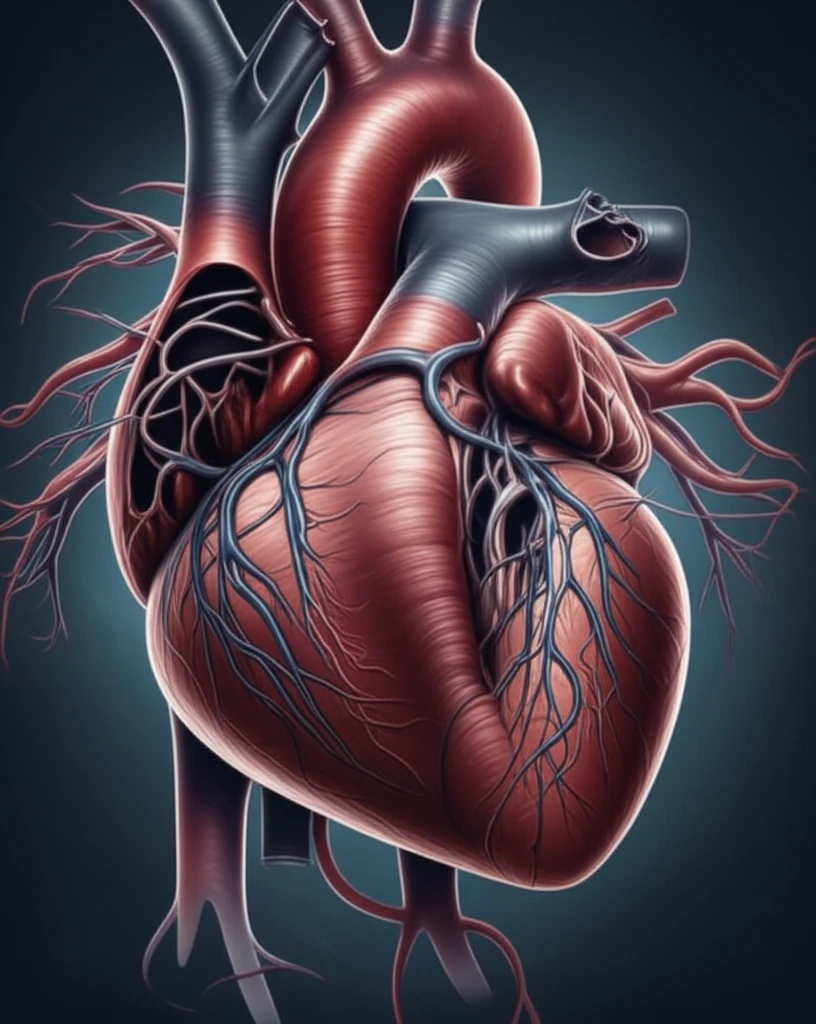

Arrhythmogenic Right Ventricular Cardiomyopathy (ARVC) is a heart condition marked by dangerous ventricular arrhythmias, an elevated risk of sudden cardiac death (SCD), and impaired right ventricular function. It's like a perfect storm in your heart, where electrical glitches meet structural changes, potentially leading to life-threatening events.

Microvascular disease occurs when the small blood vessels of the heart don't dilate properly, limiting blood flow. This can lead to chest pain and other symptoms, even when the main coronary arteries appear normal. It’s like having a hidden network of tiny blockages that starve your heart muscle of oxygen.

Normally, these conditions are seen as separate issues, but what happens when they occur together? This article explores a fascinating case study that suggests a possible link between ARVC and cardiac microvascular disease, raising important questions about diagnosis, risk assessment, and treatment strategies.